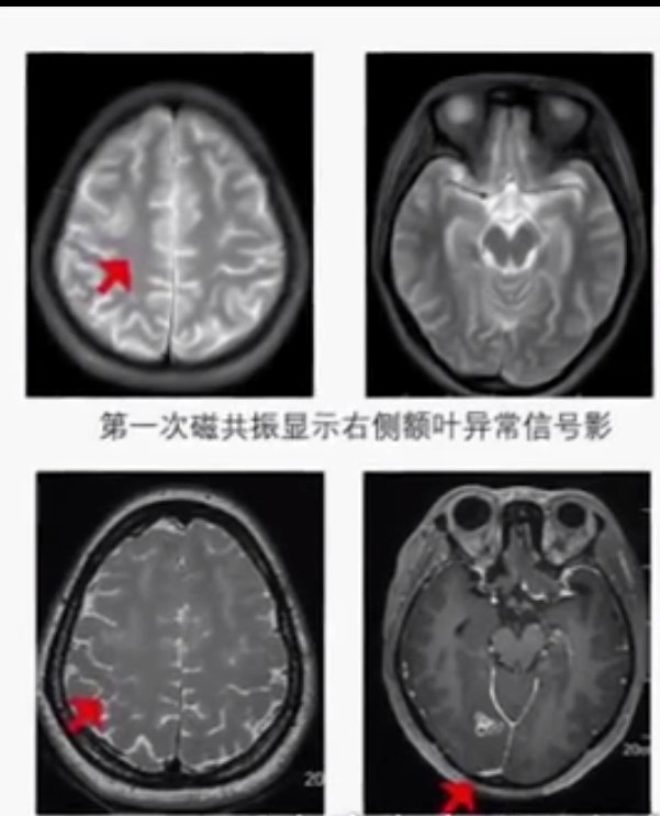

- Çin’de 23 yaşındaki ismi Chen olarak açıklanan genç, beyninde canlı kurtçukla 17 yıl yaşadı. Altı yaşından itibaren el ve ayaklarında uyuşukluk hisseden Chen, vücudunun üst sağ kısmındaki hislerini kaybedince doktora gitti. Genç adam, ameliyatla beynini yemeye başlayan kurtçuktan kurtuldu.

- Doktorlar kendisine tam pişirilmemiş kurbağa ve yılan yediği için vücudunda enfeksiyon olduğunu, enfeksiyon kaynaklı bu şikayetlerin ortaya çıktığını söylediler. Şikayetleri artan Chen, Jiangsu eyaletinde bulunan Wuchang Üniversite hastanesine gitti. Chen, doktorlara 17 yıldır el ve ayaklarında uyuşma olduğunu ve şiddetli baş ağrısı yaşadığını söyledi.

- Doktorlar tarafından beyin tomografisi çekilen Chen’in beyninde 13 santimlik kurtçuk olduğu ve 17 yıldır kurtçuğun uyuşma şikayetlerine sebep olduğunu söylediler. Daha sonra kurtçuk ameliyatla alındı.

- Kurtçuğun insan vücuduna girdiği sırada enfeksiyona sebep olduğunu söyleyen doktorlar, kurtçuğun beyni yavaş yavaş yemeye başladığını bu yüzden uyuşma ve baş ağrısı şikayetlerin ortaya çıktığını söyledi.